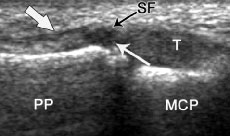

In assessing the “Skiers’s Thumb” injury your Hand Therapist, Physiotherapist or Occupational Therapist at Action Rehab Hand Therapy Clinic will have a careful look at your ultrasound and x-ray and if you don’t already have an x-ray or ultrasound your therapist might refer you for one. The Hand Therapist at Action Rehab Hand Therapy Clinic will also physically examine the joint that is injured to assess the severity of the tear and loss of function. Many times the mechanism of injury (how you hurt it) is very useful in diagnosing a Skier’s Thumb injury so the Hand Therapist at Action Rehab Hand Therapy Clinic will be sure to always ask “how did this happen?”